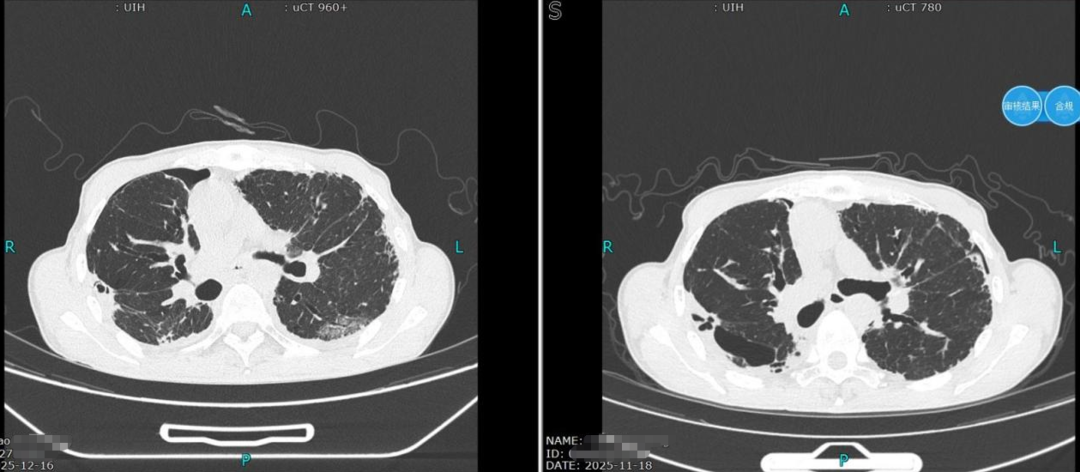

术后第9天复查胸部CT,肺组织完全复张,顺利拔除引流管;